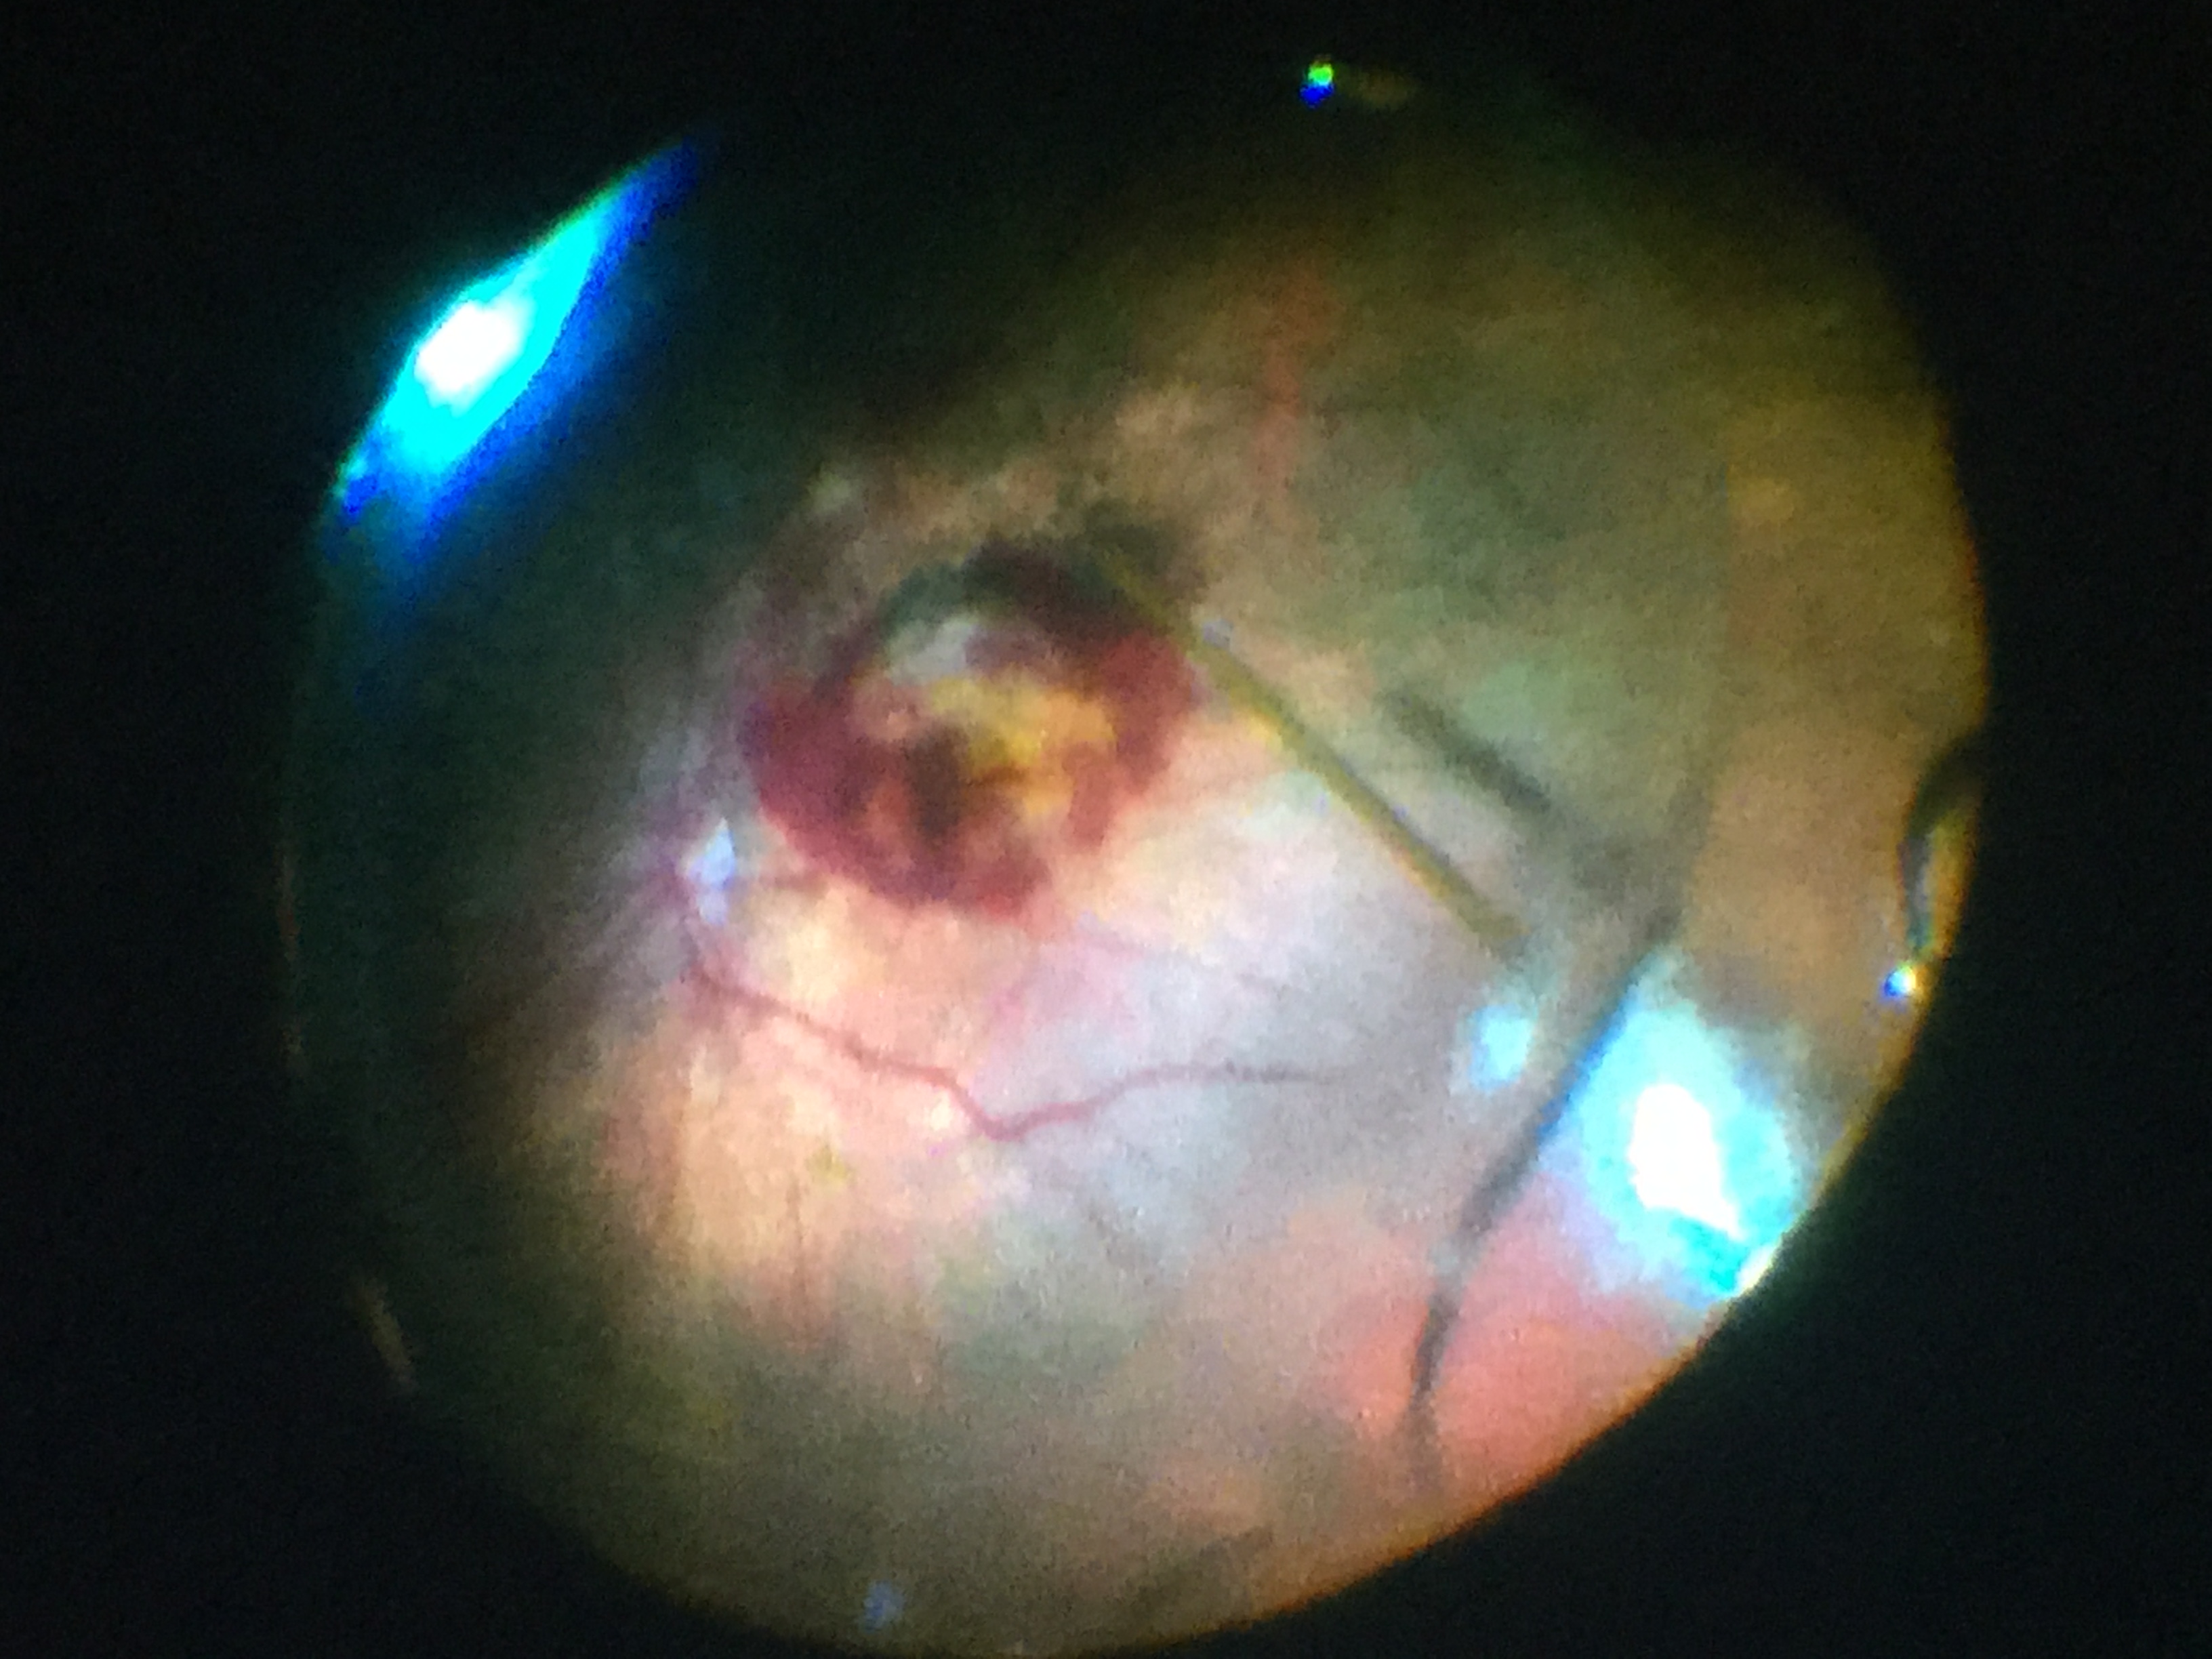

«Il diario – spiega Stefano Angioni, responsabile del Centro Endometriosi – verrà distribuito in tutta Italia ai medici di famiglia con il contributo non condizionato di una ditta farmaceutica (Bayer). L’endometriosi è una patologia frequente che colpisce le donne durante la vita riproduttiva. La manifestazione della malattia varia da piccole lesioni a cisti ovariche, fibrosi e aderenze di gravità tale da sovvertire l’apparato riproduttivo della donna. L’insorgenza è spesso precoce perfino in età adolescenziale. La malattia è causa frequente di una sintomatologia dolorosa, spesso invalidante, che comprende: dolore durante la mestruazione, dolore durante i rapporti, dolore pelvico cronico e, nel 30-40% dei casi, è associata a infertilità. A volte, soprattutto nei casi in cui la malattia infiltri altri organi, possono essere presenti sintomi intestinali e/o urinari. Esistono diverse forme di endometriosi e diverse risposte alle terapie mediche e chirurgiche.»